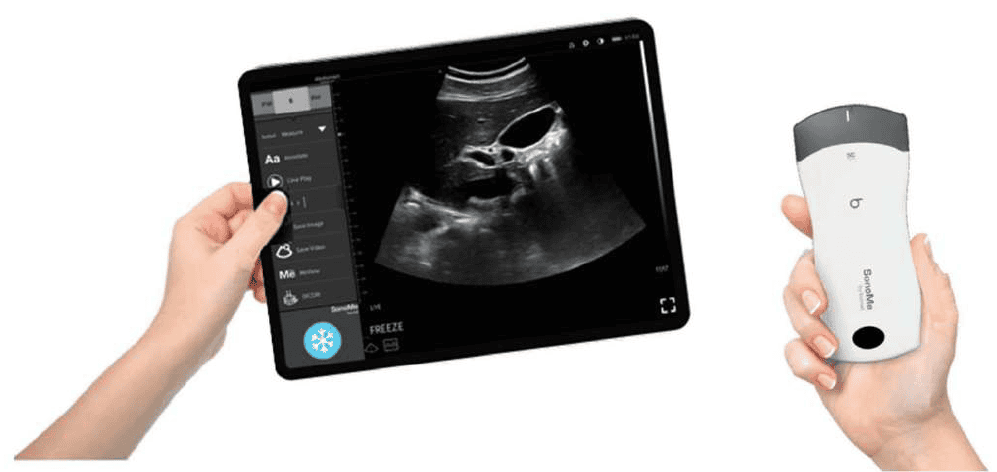

SonoMe je plně bezdrátový ruční ultrazvukový systém navržený pro point-of-care diagnostiku. Sonda se připojuje přímo k mobilnímu telefonu nebo tabletu prostřednictvím Wi-Fi, takže není potřeba žádná hlavní jednotka ani kabely.

Díky hmotnosti přibližně 260 g a kompaktním rozměrům je přístroj ideální pro rychlé vyšetření v ambulanci, na oddělení, při vizitách i v terénu.

Integrované zpracování obrazu a moderní technologie umožňují okamžité zobrazení snímků v reálném čase přímo na mobilním zařízení.

SonoMe funguje jako samostatná bezdrátová sonda s vlastním Wi-Fi připojením. Po propojení s aplikací v telefonu nebo tabletu je systém okamžitě připraven k použití.